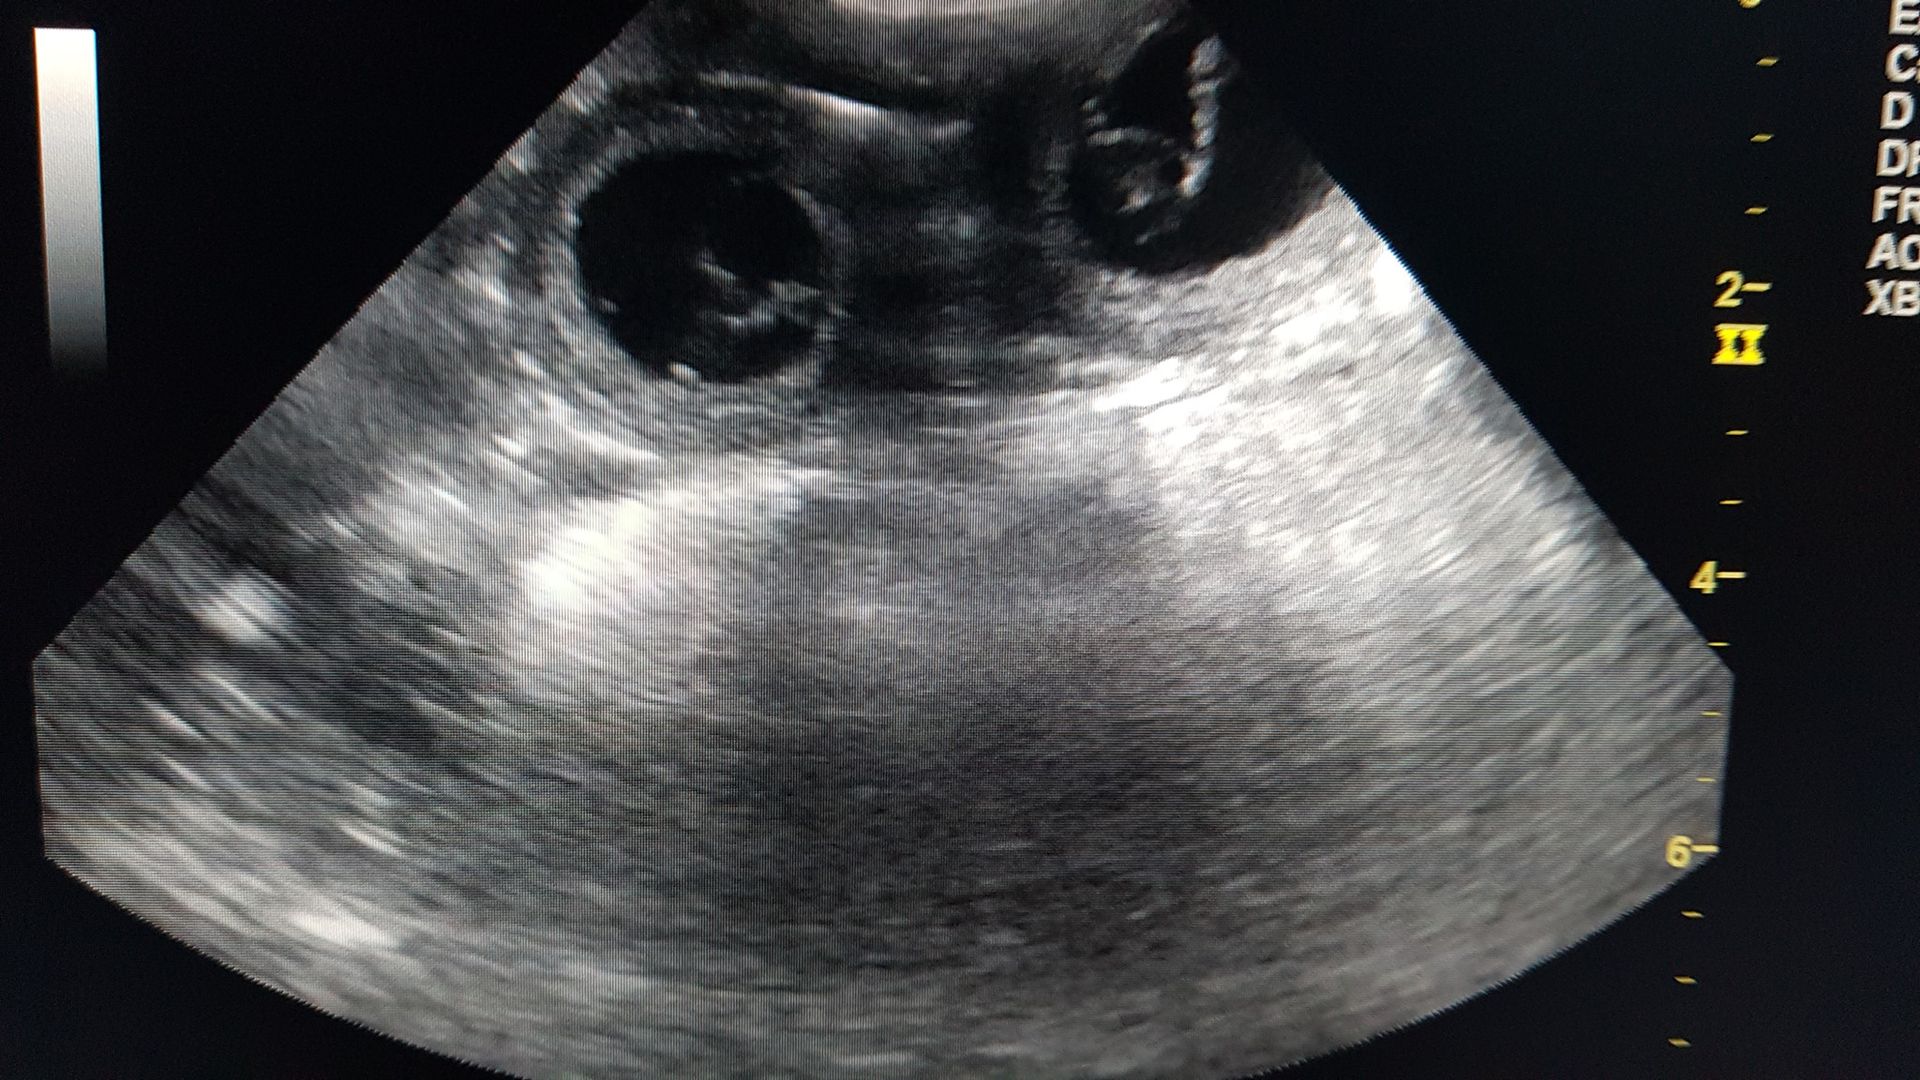

- Confirmation puis surveillance du bon déroulement de la gestation grâce aux examens échographiques.